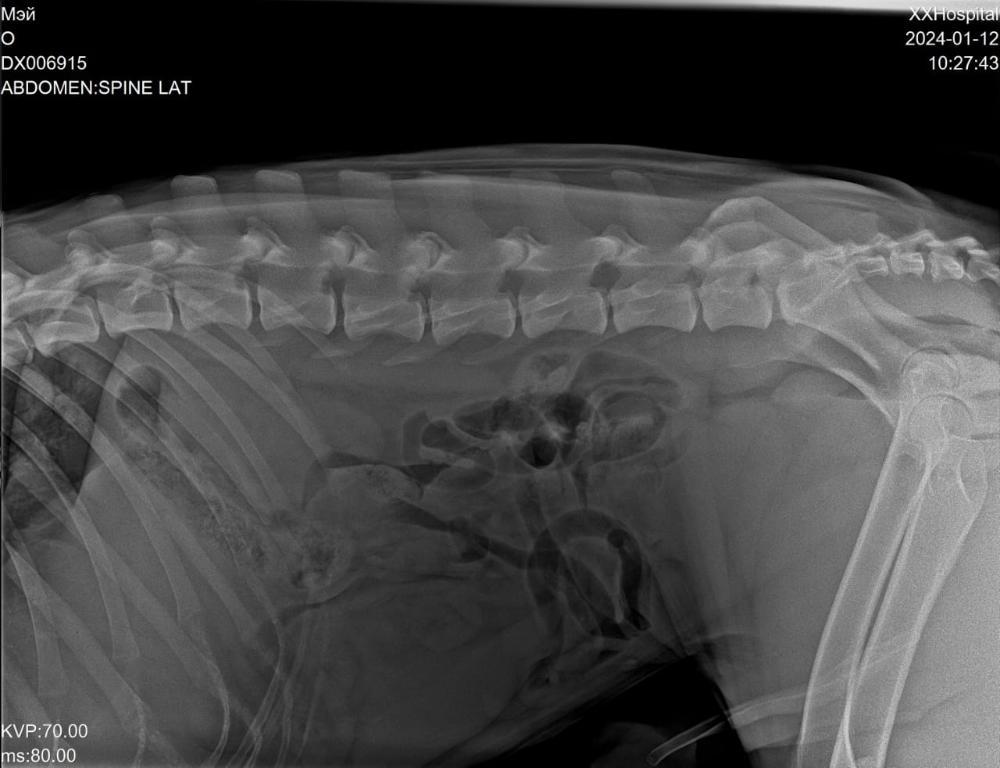

Светлана 2101 Опубликовано 12 января, 2024 Опубликовано 12 января, 2024 Сегодня съездили с Мэем к ортопеду. Сделали рентген. Сразу скажу, я осталась очень довольна приемом, содержательной беседой с врачом. Но есть новости хорошие и не очень. Сделано - рентген грудной и поясничный отдел, тазобедренных суставов и рентген оперированной лапы. По позвоночнику - в прекрасном состоянии, нет признаков травмы и дегенеративных изменений, кроме единичного незначимого очага дискоспондилита в среднем грудном отделе. На одном позвонке только есть изменения ( на снимке красным). Это ни о чем .Никак на жизнь не влияет. Тазобедренные суставы в отличном состоянии, без признаков дисплазии. В оперированной лапе - конструкция стабильна, признаки консолидации отломков. То есть всё хорошо. Доктор сказал, что далее ещё больше укрепляться будет. Процесс нарастания костной мозоли ещё идёт. Новости не очень. Измерил угол наклона плато, это крепление связок. Не очень владею всеми терминами, но своими словами напишу, как поняла. Этот угол у Мэя 20°, норма 14, при значении 25 и выше сто процентов разрыв ПКС неминуем. Хоть доктор и написал в заключении, что риск разрыва ПКС невелик, но на словах мне сказал, что вероятнее всего рано или поздно связки порвутся. 20° это уже большое натяжение, рвутся и при 22-23. Соответственно, рекомендации режим спокойных прогулок в монорежиме без кучных игр для минимизации нагрузки на коленные суставы . То есть спокойный режим даже не столько для оперированной лапы, сколько угроза разрыва ПКС. По словам доктора, это генетическая предрасположенность. В беседе он так сказал, что, да вы можете стараться его ограничивать от прыжков, но один раз он не прыгнет, а в другой раз всё равно прыгнет. Теперь вы знаете, что можно ожидать, но совсем собаку не ограничить во всем. А Мэй как раз очень прыгучий. Он даже на подзыв не просто подбегает, а прыгает.И бежит он прыжками. Один плюс, что он не знает диванов, и нет этого туда-сюда по 20 раз в день. Но на улице он хочет бегать. И бегает он очень мощно.Теперь понятно, что надо помнить об этом и стараться минимизировать прыжки . Но до сих пор связки целы, а прожил он с ними уже несколько лет, и режим у него был наверняка активный, никто его не ограничивал. Есть надежда, что продержатся они и ещё. И опять здесь очень хорошо, что он на НП, натуральные коллагены и Хондроитины помогут укреплению связок и сохранят суставы и позвоночник ,которые сейчас в прекрасном состоянии . Вот такое обследование. Я очень рада, что нет проблем в позвоночнике и суставах. Но не без ложки дегтя. Всё равно спокойный режим прогулок и жизни. А там как сложится. Просто теперь мы об этом знаем, что можно ожидать . 4 3

Светлана 2101 Опубликовано 12 января, 2024 Опубликовано 12 января, 2024 Рентген грудного отдела, вот единственный позвонок с дискоспондилитом, остальные все красивые Рентген пояснично крестцового отдела. Без изменений. Рентген тазобедренные. Рентген конструкции на оперированной лапе и углы. 5